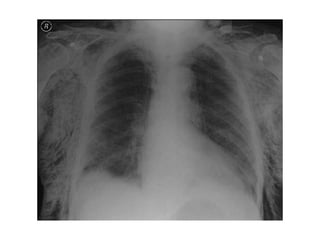

Hemotórax

Quando suspeitar? na presença de:

• Taquipnéia;

• Dor torácica;

• Respiração superficial;

• MV ausente ou diminuído do lado afetado;

• 90% dos casos o tratamento é eficiente

apenas com drenagem.

• 10% é necessário intervenção cirúrgica,

toracotomia ou laparotomia exploradora.

• Pode apresentar -se normotenso ou

hipertenso.

• Quando hipertenso está associado a

pneumotórax.

• Macicez à percussão do hemitórax afetado;

• Sinais clínicos de choque (cada espaço pleural

pode reter até 2500 a 3000 ml de sangue,no

adulto);

• Confusão mental e ansiedade, dependendo da

magnitude do comprometimento respiratório e

cardiovascular;

• Pensar na associação com pneumotórax,

especialmente nos traumas penetrantes.

O sangue coletado na cavidade pleural tem

4 origens:

• Parênquima pulmonar (90% dos casos);

• Vasos sistêmicos (intercostais,

mamários);

• Lesões de mediastino (coração, vasos da

base);

• Ferimentos toraco-abdominais

Classificação

• Pequeno: 300 a 350 ml de sangue

drenado

• Médio: 350 a 1500 ml de sangue drenado

• Grande: maior que 1500 ml

• Tratamento

• Drenagem torácica